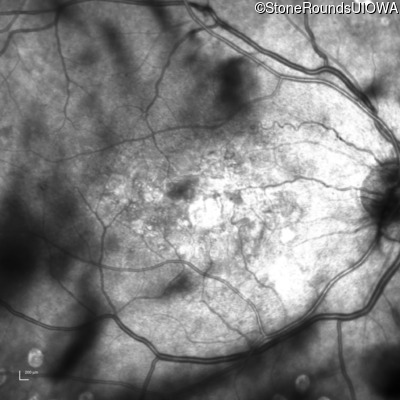

Malattia Leventinese (IIJ)

Malattia Leventinese (IIJ)

This 43 year old woman has experienced a gradual reduction in her central vision for the past 3 years.

| Malattia Leventinese | EFEMP1 | Arg345Trp CGG>TGG | AD |